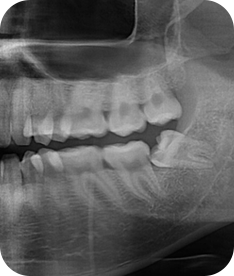

치주치료 전후사진

B

A

치주치료

청담네오플란트는 치주치료를 통하여 치아를 살릴 수 있는 기회를 놓치지 않습니다.

치주염(잇몸병)은 치아에 붙어있는 치석 및 세균 등에 의한 염증반응으로 잇몸뼈가 상실되는 질환을 말합니다.

초기에는 잇몸이 붓거나 잇몸에서 피가 나는 증상이 나타나며 계속 방치하면 치아를 발치해야 할 수도 있습니다.

치주치료는 이러한 치석 및 세균 등을 제거하여 잇몸뼈를 안정된 상태로 유지하는 시술을 말하며, 청담네오플란트에서는 치의학박사 / 전문의가 직접 시술하고 있습니다.

치주염 단계별 증상

건강한 상태

치아 주위의 잇몸이 핑크색을 띄며, 잇몸에서 피가 나지 않음.

스케일링을 6개월 ~ 1년 주기로 받고 올바른 칫솔질로 건강한 치주 조직을 유지

치은염 (초기~중기)

치아 주위의 잇몸이 붉게 부어 있으며, 칫솔질 등을 할 때 피가 남.

스케일링 주기의 조절이 필요할 수 있으며, 올바른 칫솔질을 시행하여야 함.

치주염 (중기~말기)

주기적으로 잇몸이 붓고 피가 나며, 욱씬하거나 우리한 통증이 나타남.

치주치료 및 정도에 따라 치주수술(잇몸수술)이 필요함. 향후 관리 정도에 따라 3~6개월 간격으로 내원하여 유지치료를 시행하여야 함.

치주염 (말기)

잇몸이 항상 부어 있으며, 이가

흔들리는 정도가 점점 심해짐.

치주치료가 필요하며, 정도에 따라 치아를 발치하여야 할 수 있음.